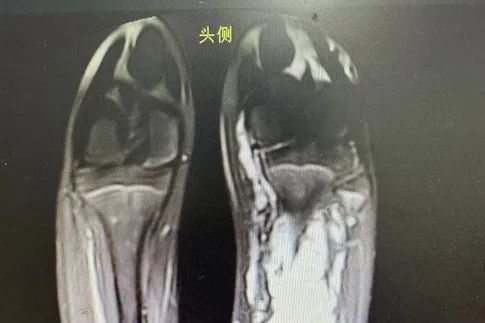

无独有偶,11岁的小邓(化名)随着年龄生长,膝盖和脚底存在不同程度的肿胀、青紫现象,就像一条条正在蠕动的“虫子”。医生检查后明确诊断为左下肢静脉畸形。家长带着孩子曾多次在广州某医院做治疗,但是效果欠佳,而且在外地诊治花费较大。

得知桂林市妇幼保健院一直开展有血管畸形治疗业务,于是前来求助。经过医患双方讨论,最终决定开展局部注射硬化治疗。经两次硬化治疗后,小邓下肢酸胀、疼痛感明显好转,从外观看曲张的静脉明显减少,家属对治疗效果比较满意,目前已出院。

静脉畸形是一种先天性的血管发育异常,表现为皮肤或黏膜下的蓝色或紫色团块,常出现在头颈部、四肢或口腔内。它由一团杂乱增生的静脉血管构成,并非肿瘤,但可能随年龄增长而扩大,导致疼痛、肿胀甚至影响器官功能。临床上通过超声、磁共振(MRI)等检查可明确诊断,典型特征包括“体位试验阳性”(按压后肿块缩小、松开后复膨)。